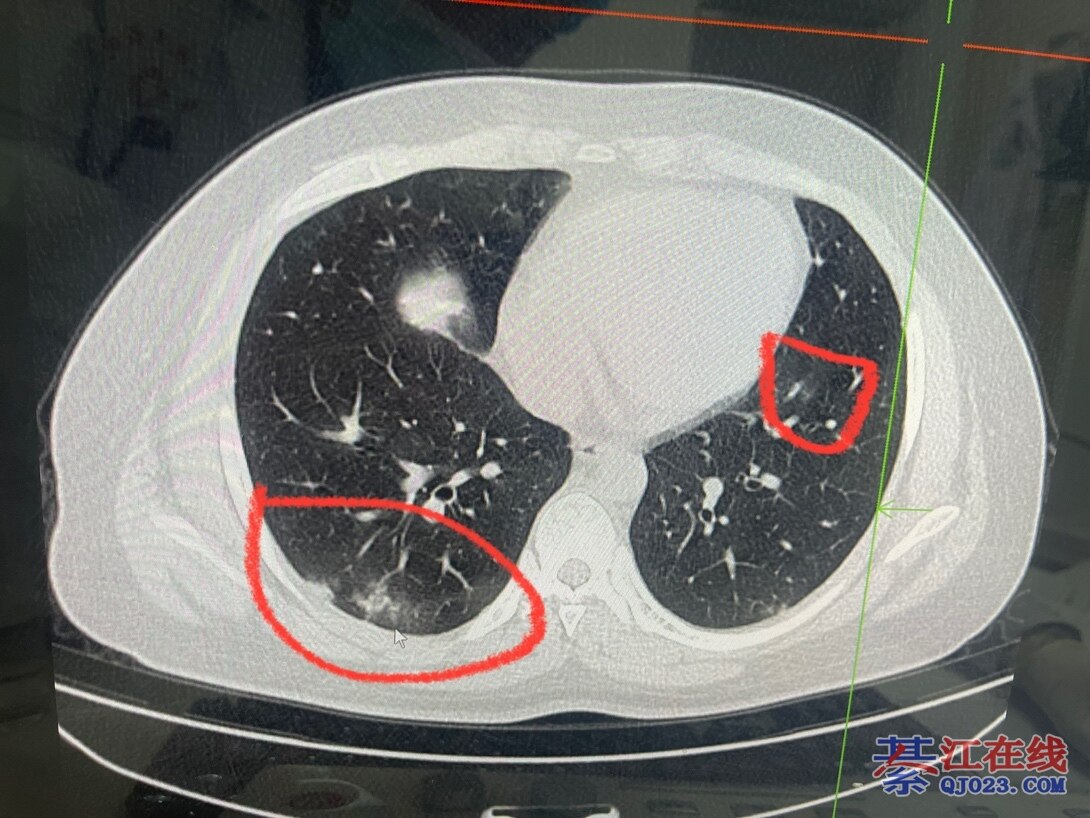

信了楼主的话,今天去做了CT,右肺中叶磨玻璃影,符合新冠病毒肺炎表现。阳了13天,症状早已消失,但是肺上还是有问题。

楼主应当注意的一点是, 阳康了,还是伴有剧烈咳嗽,并发胸痛呼吸困难这种, 实打实的身体非常不舒服了, 这种需要去医院做个CT看看,不是每个人都需要这样

,只是友情提醒大家一下

谢谢,因为身边有人现在没症状了,却检查出双肺感染,所以才好心提醒大家。信就信,不信就算了!不管别人怎么说我